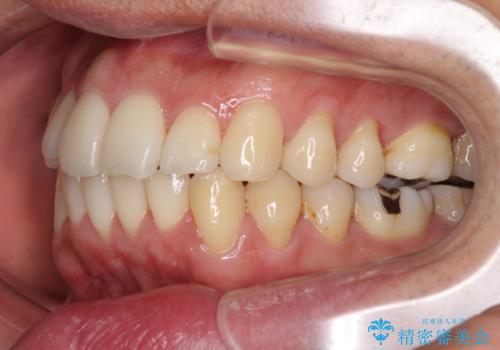

- 上下前歯のデコボコを気にして来院された患者様です。

下顎骨が顕著な左右差を持って成長したため、右側にずれている状態でした。

デコボコは抜歯をすることなく解消できる程度であったため、インビザラインにより矯正治療を行うこととしました。

この方は元々骨格的な偏位が大きかったためか、治療中に下顎骨が上顎骨よりも右外側に誘導されて、右側の奥歯が全く咬合しない状態が続いてしまいました。